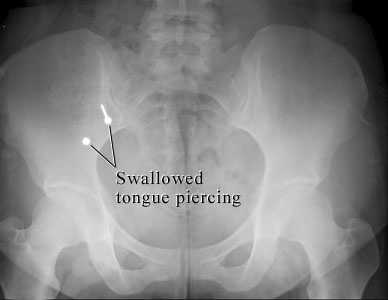

This X-ray of the belly shows two metal parts inside the bowel that were swallowed from a tongue piercing. The sharp stud could cause problems, while the blunt part is not likely to cause problems. Both parts are likely to pass in the stool.